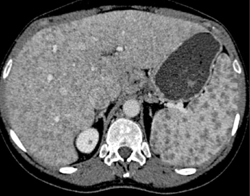

Sarcoidosis